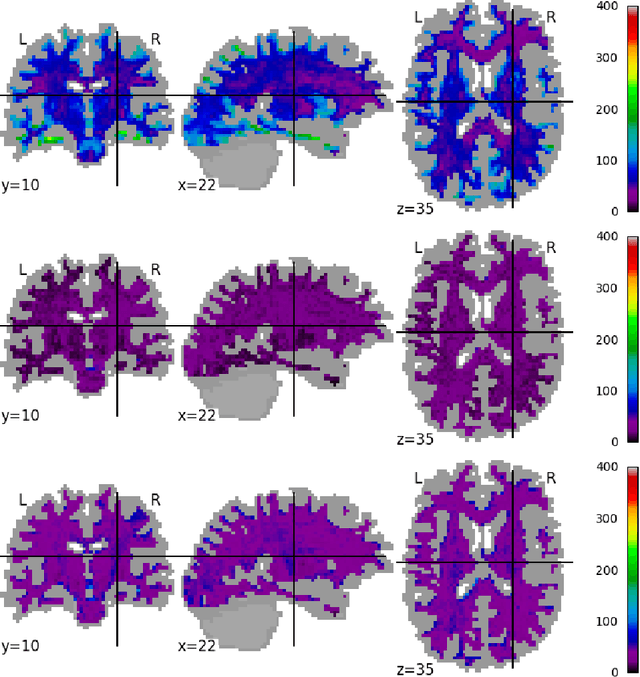

Abstract:Diffusion imaging is an important method in the field of neuroscience, as it is sensitive to changes within the tissue microstructure of the human brain. However, a major challenge when using MRI to derive quantitative measures is that the use of different scanners, as used in multi-site group studies, introduces measurement variability. This can lead to an increased variance in quantitative metrics, even if the same brain is scanned. Contrary to the assumption that these characteristics are comparable and similar, small changes in these values are observed in many clinical studies, hence harmonization of the signals is essential. In this paper, we present a method that does not require additional preprocessing, such as segmentation or registration, and harmonizes the signal based on a deep learning residual network. For this purpose, a training database is required, which consist of the same subjects, scanned on different scanners. The results show that harmonized signals are significantly more similar to the ground truth signal compared to no harmonization, but also improve in comparison to another deep learning method. The same effect is also demonstrated in commonly used metrics derived from the diffusion MRI signal.